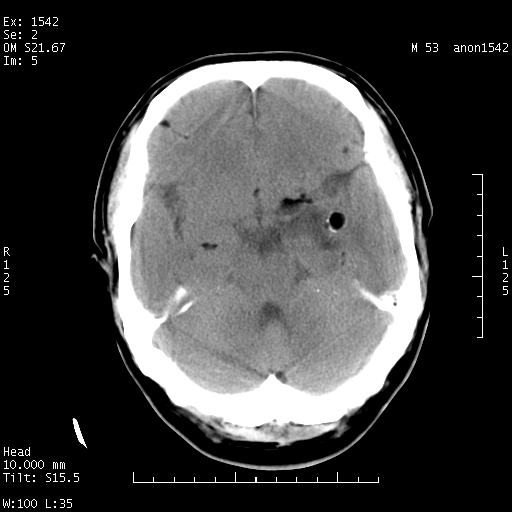

左侧鞍旁不规则低密度,此区域和侧脑室有液平。若无外伤史。考虑左侧鞍旁表皮样囊肿自发破溃。

鞍旁颞叶低密度灶.其中散在空气影.还有侧脑室.是否考虑脑脓肿(请提供病史情况)

有肿瘤样病变破溃,沿外侧裂生长,为什么不考虑胆脂瘤?

1 囊性肿物. 2 请楼主上传介少病人资料. 3 表皮样囊肿或胆脂瘤都在考虑范围内,确切的不知ct值是多少.4了解病史后在缺定.